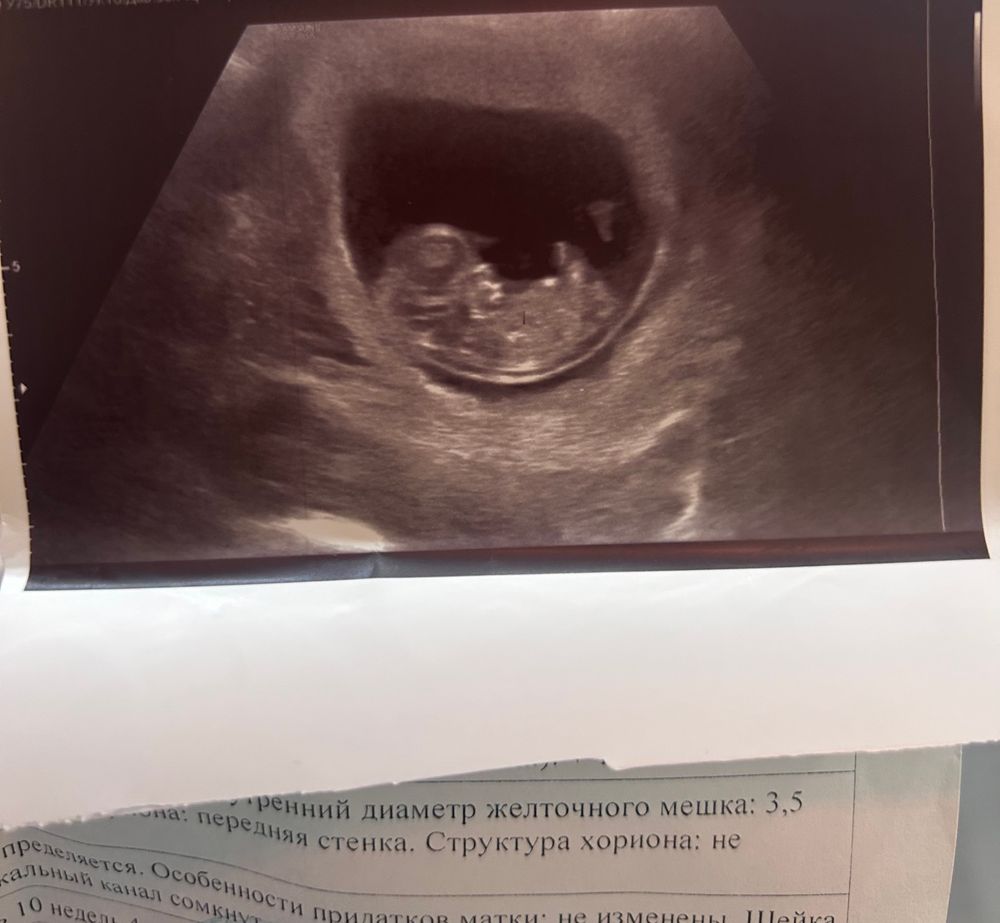

Всем привет , девочки скажите пожалуйста у меня 10 недель , пол на кого похож??

У вас уже 1ый скрининг? Поздравляю!) а пол, если честно, пока 100% определить трудно, после 20 ти недель уже пол можно будет определить.